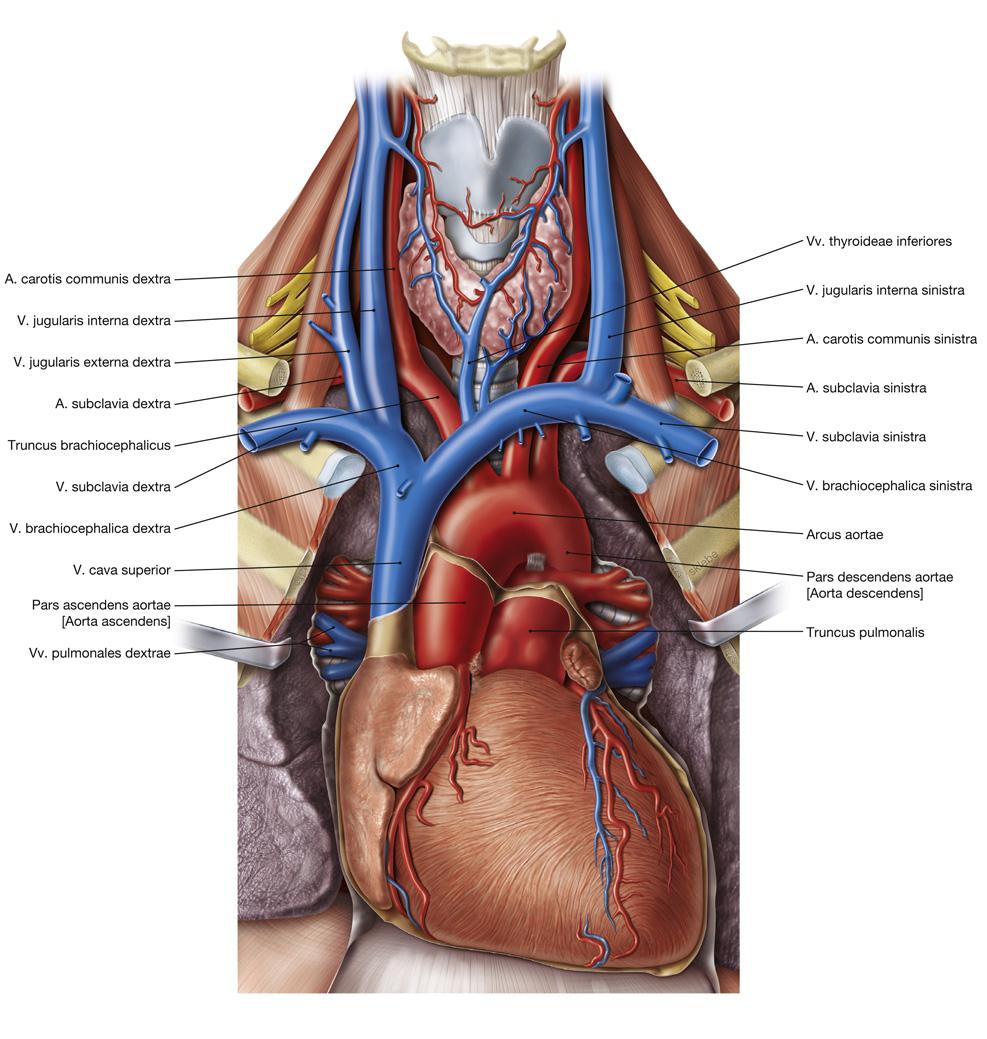

Fig 3.31: v. cava superior

distaal (vanaf elleboog, knie): diepe venen ontdubbeld aorta truncus pulmonalis -

atrium dextrum (RA)

-

v cava superior (VCS)

-

v brachiocephalica dextra (korter dan sinistra)

-

v brachiocephalica sinistra = v. anonyma = v. innominata

v azygos (oranje, posterior)

-

kleinere takken (minder klinisch belang, veel variatie)

mediastinale takken v intercostalis superior sinistra plexus (venosus) thyroideus impar v vertebralis dextra (vaak geen sinistra) v thoracica interna v cervicalis profunda

|

Sobotta: Fig 5.18